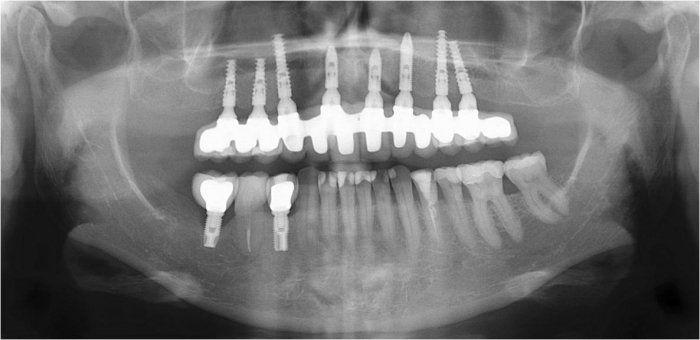

Raio x inicial

Raio x após enxerto de ilíaco

Raio x após instalação dos implantes superiores Cone Morse

Raio x após prótese fixa provisória instalada

Raio x final